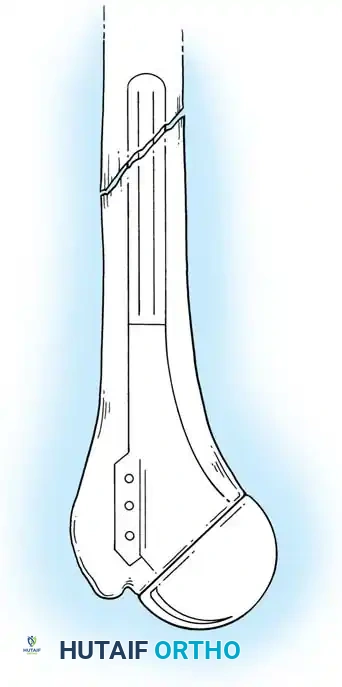

3. Canal Preparation and Implantation

The humeral and ulnar canals are sequentially broached.

- A cement restrictor is placed in both canals.

- Antibiotic-loaded polymethylmethacrylate (PMMA) bone cement is injected in a retrograde fashion.

- The components are inserted, and the articulation is linked using the manufacturer-specific locking pin mechanism.

Surgical Warning: The ulnar component must be inserted with precise rotational alignment. Malrotation will lead to eccentric wear of the polyethylene bushings and early catastrophic failure of the linkage mechanism.

- Aseptic Loosening: The most frequent long-term complication due to the high lever-arm forces across the constrained hinge.

- Periprosthetic Fracture: Particularly common at the tip of the humeral or ulnar stems due to stress shielding and osteoporotic bone.